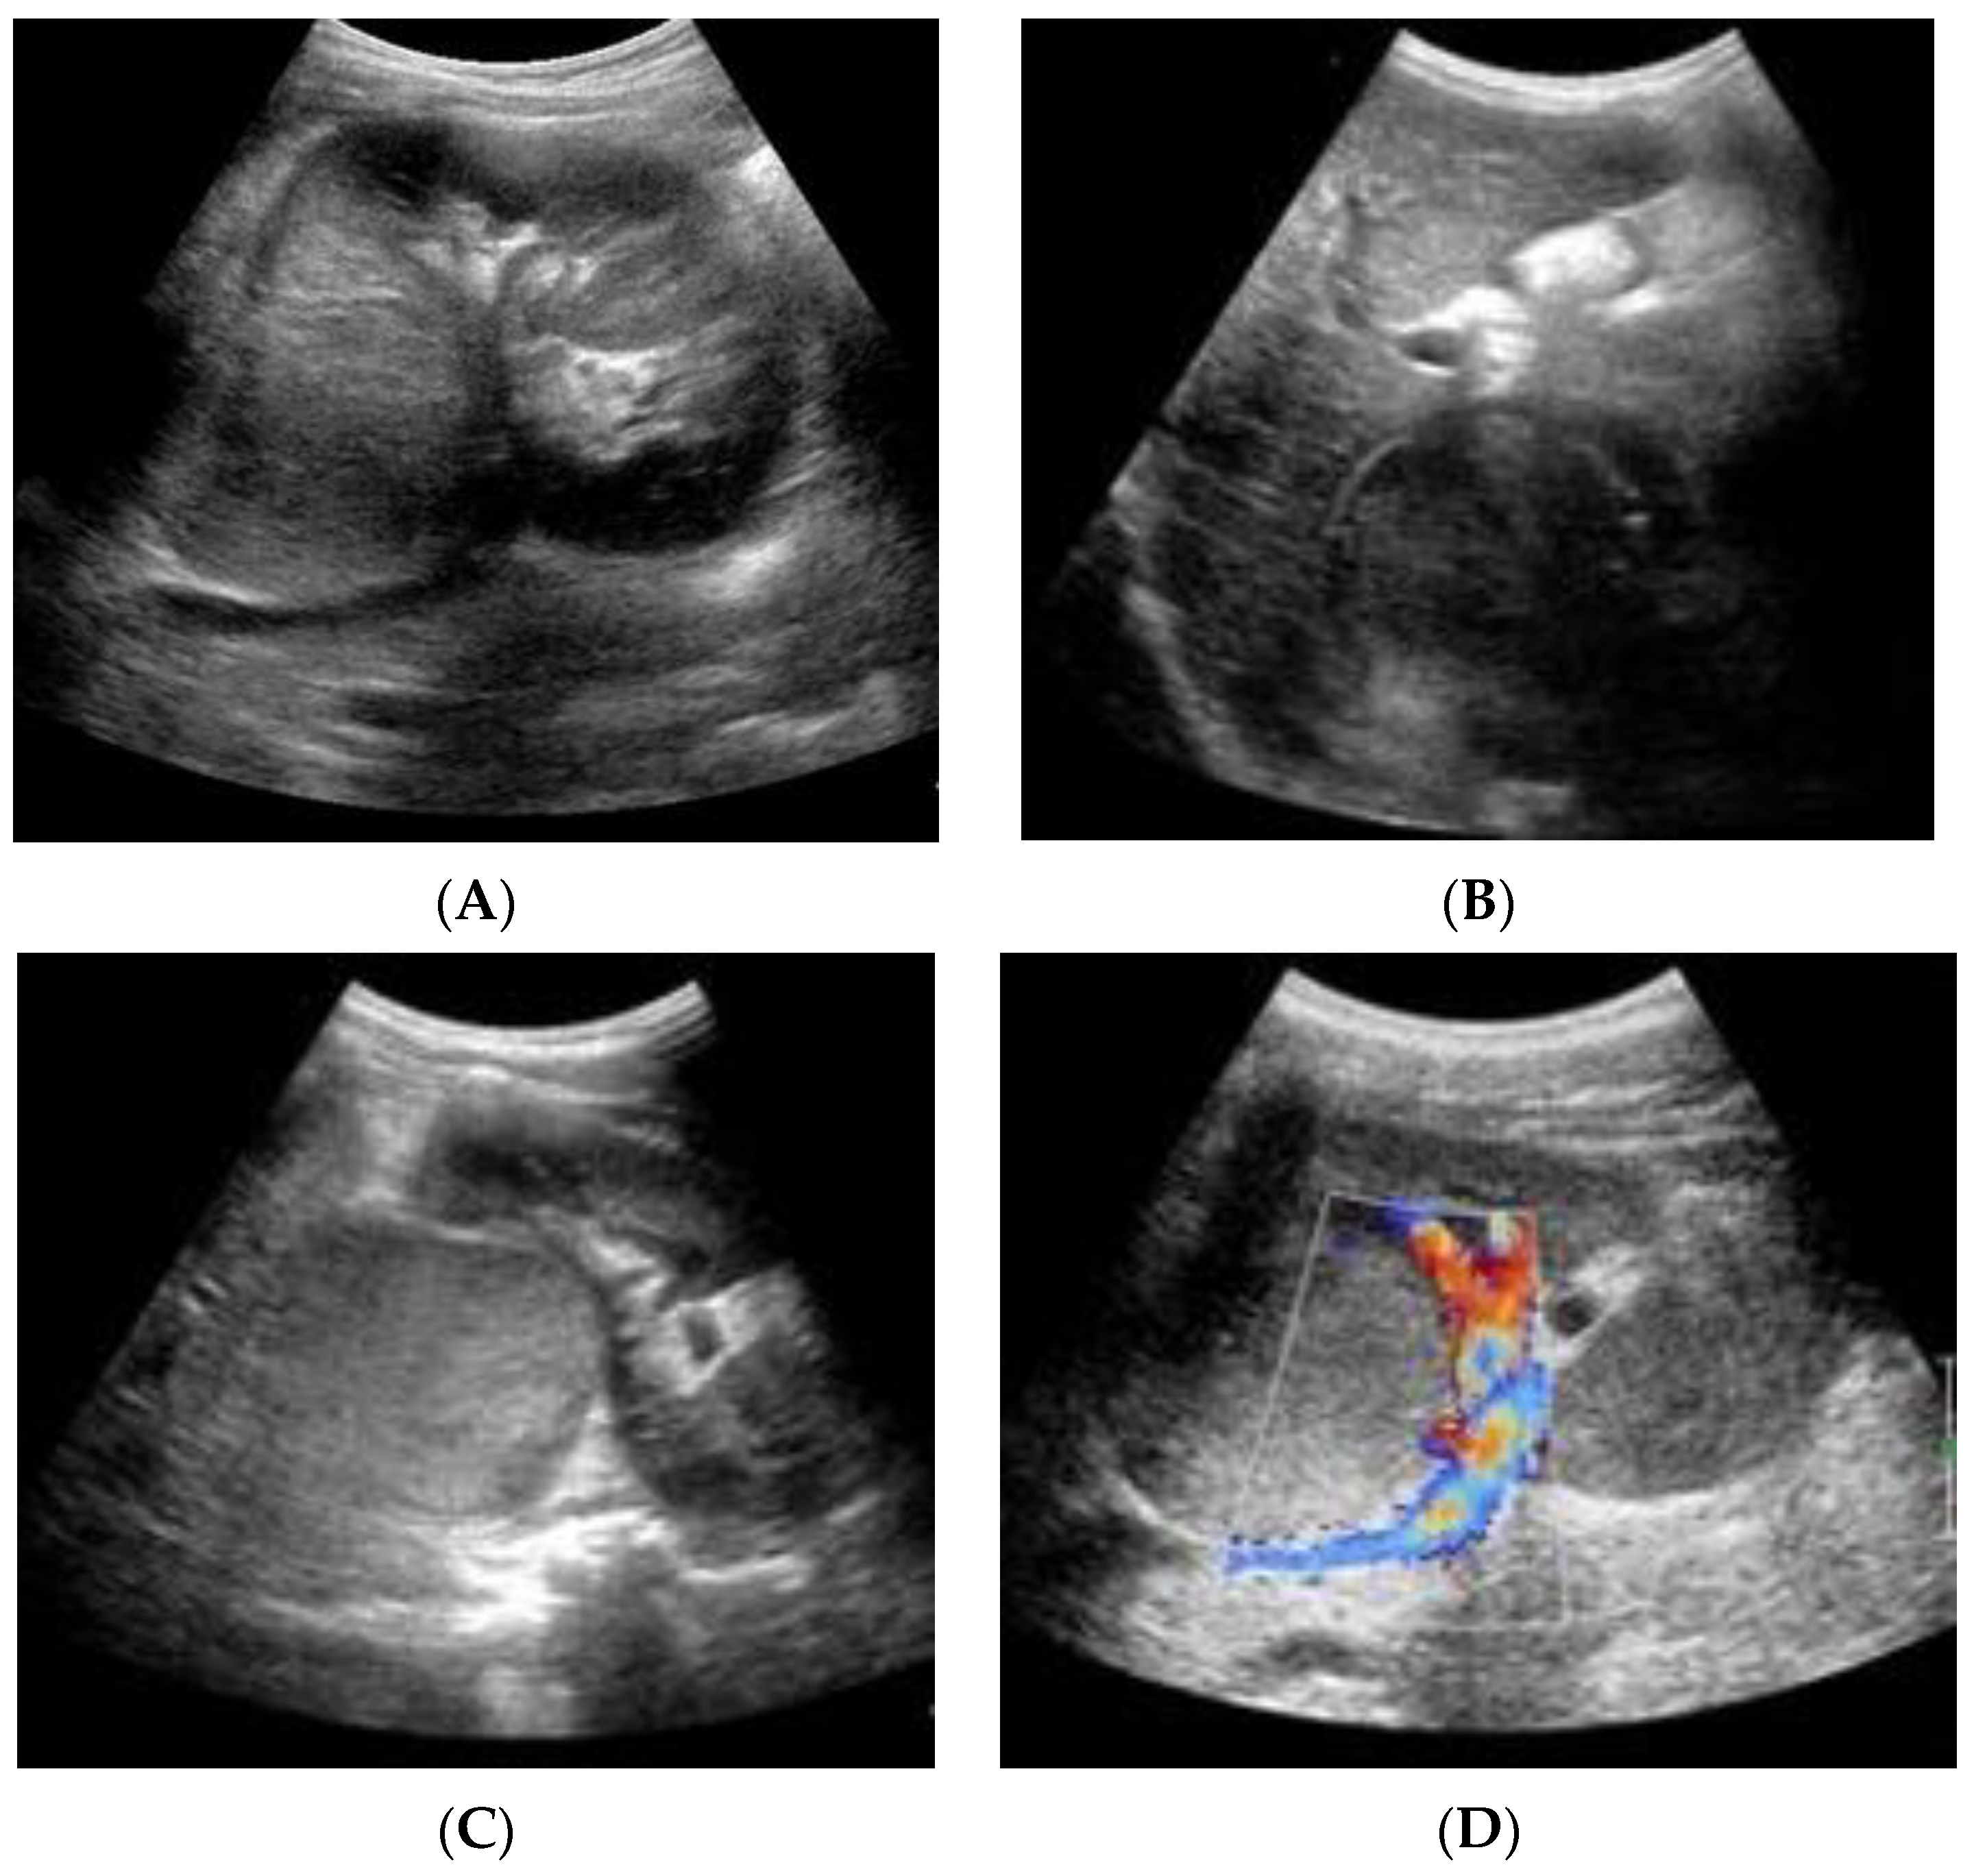

2. Case Report